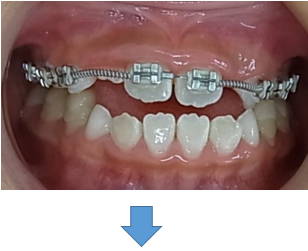

はじめに目立たないブラケット(歯に付ける矯正装置)を利用して上顎から歯並びを改善します。その折に同時にレジンを利用する事で咬み合わせの高さも挙上していきます。

歯並びを改善すると受け口がひどく見える時もありますが心配ありません。

次にMEAW(マルチループ)を利用する事で咬み合わせの高さや咬み合う平面の角度を変える事で歯(第一小臼歯)を抜く事無く受け口(下顎前突)を改善していきます。

また、MEAW(マルチループ)はゴムを24時間使用する事で最大の効果を発揮することが出来ます。